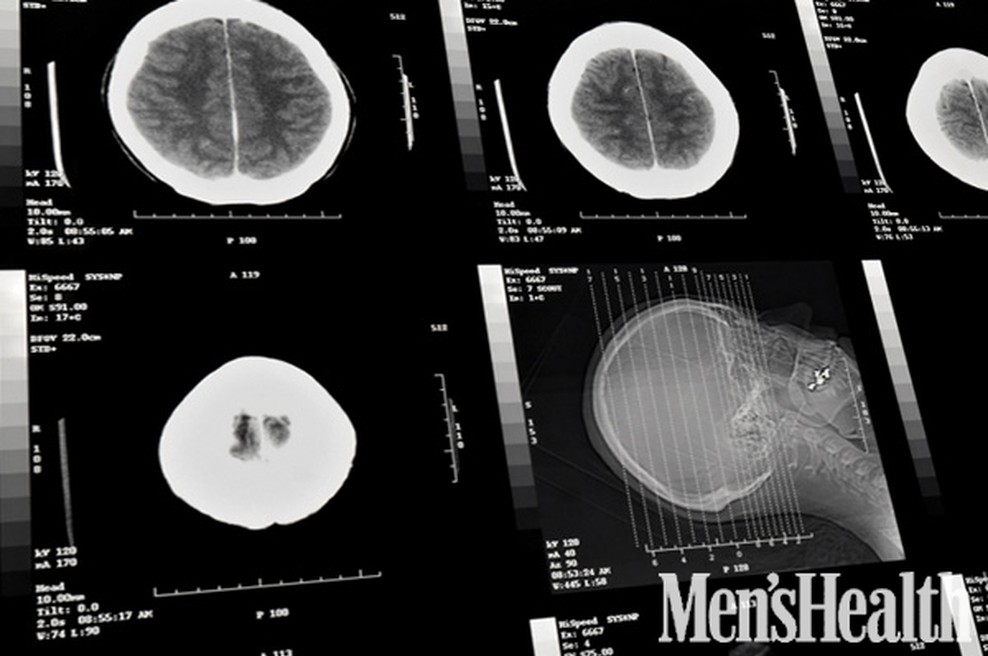

Da se Houben vsega zaveda so ugotovili šele po pregledu s posebno napravo za pregledovanje možganov, ki pred dvema desetletjema še ni bila na voljo. Njegova starša sicer vsa ta dolga leta nista hotela sprejeti diagnoze zdravnikov in sta bila prepričana, da se njun sin zaveda dogajanja okoli sebe. Izkazalo se je, da sta imela prav.